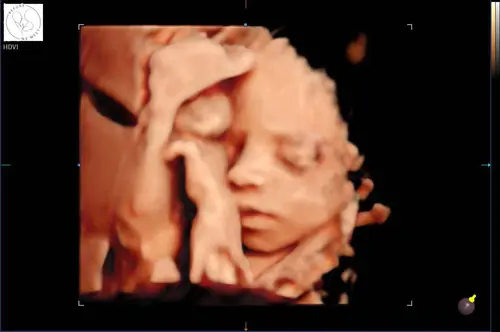

Dit was de echo van ons ventje... al met 22 weken gedaan toen ik in Nederland was. Vandaag 27 weken alweer.